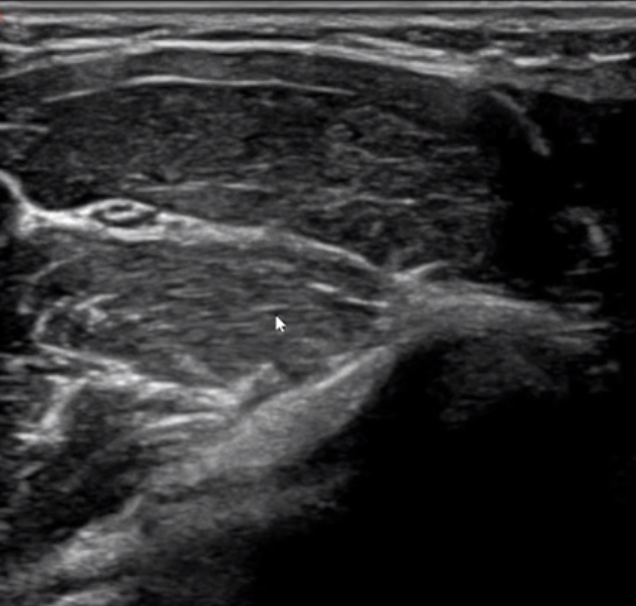

术中,医生把B超探头放到小晟皮肤表面,一旁的屏幕上就出现了骨折处的图像。在超声引导下,沈先涛将克氏针精准“插入”肌肉,复位“对齐”后打上石膏固定,手术顺利完成,全程没用X射线透视定位。

二维肌骨超声图像